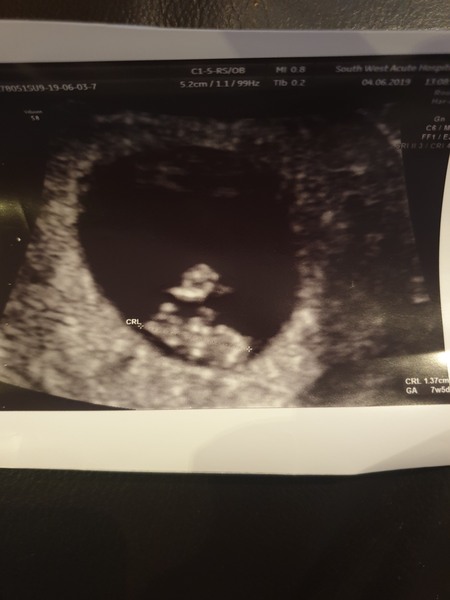

Hey all, hope everyone is well. Went to gp this morning with a suspected kidney infection, she referred me for a scan with epu as urine was clear but intense pain in lower right groin and abdomen, was so unexpected but glad i got to see my little bean and a strong heartbeat. All looks well in gyne end (ive had large ovarian cysts in the past) so have been referred to xray department for further urinary tract scans (they think kidney stones??)

My Scan went well measured perfectly for my dates and baby was moving around really sweet. I think I may leave this one as a surprise as I have a boy and a girl already but what puts me off doing that is not being able to buy pink or blue clothes! X

I'm 8+2 today based on dates, but I was measuring about a week less than my dates when I went for my first scan a week ago ... so will know more tomorrow - hopefully! These first 12 weeks are just the worst!